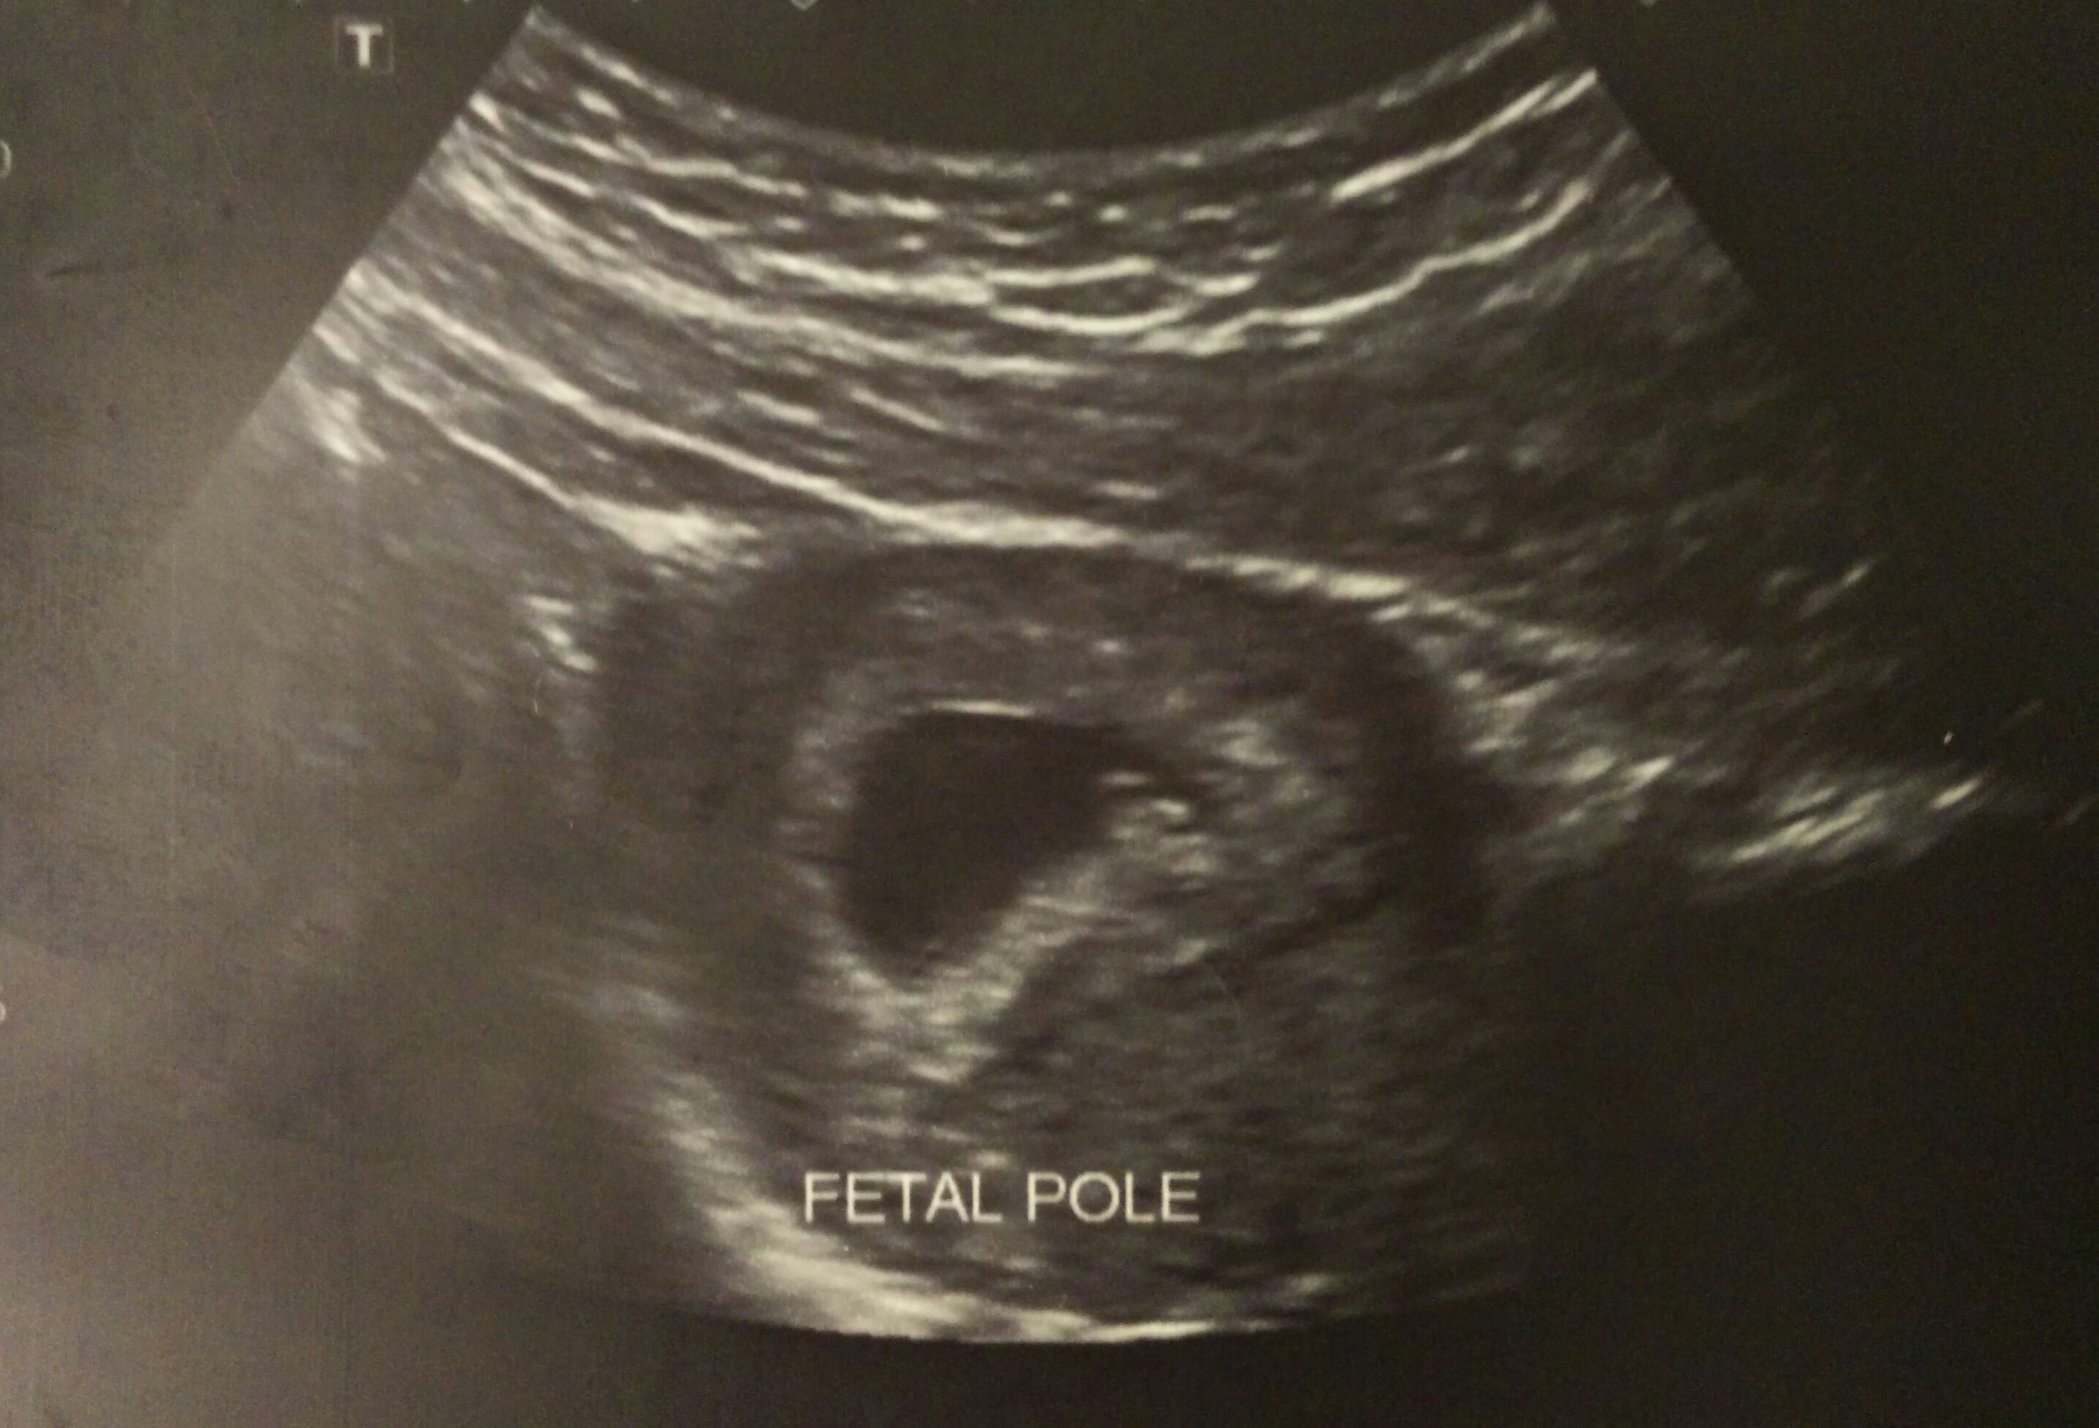

I had my second ultrasound today after my first one two weeks ago was only showing a gestational sack. I was worried something was wrong, but when I went in this morning the baby was measuring a week behind at about 7 weeks and had a heart rate of 141!! Silly me forgot to ask for a picture, though.